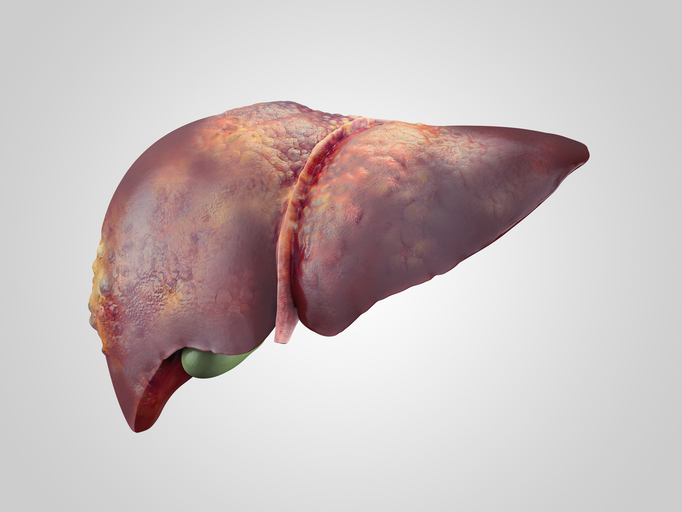

Bile function and liver: Foods that help increase bile production

Bile is produced by the liver and is used to aid in proper digestion. It helps the body eliminate waste from the blood. The salts found in bile can emulsify fat and break it down into smaller particles. Bile can help the body absorb those broken down products of fat within the gut. As mentioned, bile is ...click here to read more